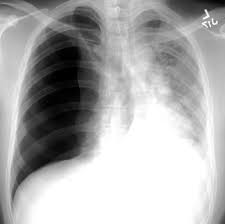

what pathology does this image show

pneumothorax